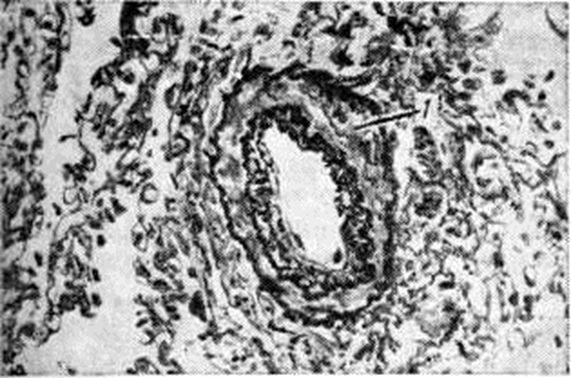

При посткапиллярной форме нарушение оттока из лёгочных вен приводит к гипертрофии мышечных элементов мелких вен лёгкого с последующим склерозом стенки, что вызывает сужение их просвета (рисунок 4). Это наиболее выражено в нижних долях лёгких. Мелкие ветви артерий терминальных и респираторных бронхиол суживаются вследствие гипертрофии средней оболочки (рисунок 5), иногда склероза внутренней оболочки, что является результатом их рефлекторного спазма. В мелких артериях отмечается миоэластоз с последующим фиброзом средней оболочки; капилляры дольше других отделов сосудистого русла лёгких остаются неизменёнными, лишь в стадии декомпенсации отмечается фиброз их стенки и появление сидерофагов (альвеолярные макрофаги, заполненные гемосидерином).